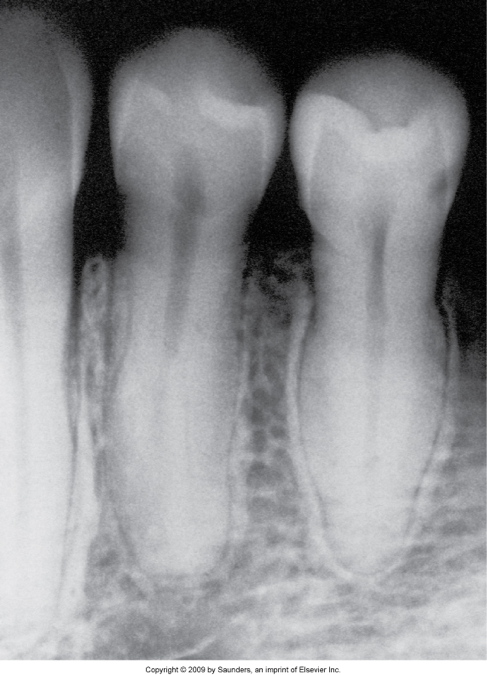

Taurodontia